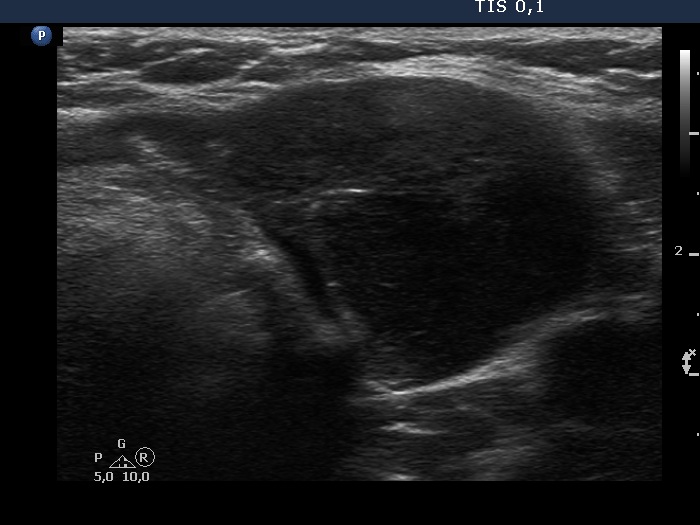

Second examination 3 years later (second, fourth and sixth rows of images):

Ultrasonography. Compared with the previous examination, both the number and the size of discrete lesions in the thyroid have increased.